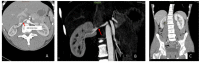

Background Fibromuscolar dysplasia (FMD) is an idiopathic, non-atherosclerotic and non-inflammatory stenotic lesion of renal arteries causing renovascular hypertension up-regulating renin-angiotensin-aldosterone system. Case report: A 18-year-old man was referred to our Hypertension Center (Clinica e Terapia Medica) for the recent onset of hypertension, poorly controlled on calcium channel blockers, already associated to electrocardiographic and echocardiography signs of left ventricular hypertrophy and significant albuminuria (728 mg/24 h). An increased plasma renin activity (PRA), aldosterone level and a mild hypokalemia raised the suspicion of renovascular hypertension. Abdominal CT and MRI angiography showed mild kidneys asymmetry and a tubular stenosis of the right renal artery in its mid-distal portion close to renal hilum. Radionuclide renal scintigraphy documented a kidneys asymmetry of separated glomerular filtration rate. Renal FMD was diagnosed based on patient age and the absence of cardiovascular risk factors for atherosclerosis. Patient successfully underwent right renal angioplasty giving a rapid normalization of blood pressure levels without antihypertensive drugs. Plasma aldosterone and PRA rapidly normalized as well as serum potassium levels. Six months after angioplasty echocardiography showed a regression of left ventricular hypertrophy and the patient albumin urine excretion became normal (14 mg/24 h). Conclusions FMD can cause renovascular hypertension associated to organ damage such myocardial hypertrophy and albuminuria through mechanisms dependent but also independent from blood pressure levels. Renal angioplasty turned off renin-angiotensin-aldosterone overactivity allowing the cure the hypertension and a surprisingly rapid reverse of myocardial hypertrophy and of excess of albumin urine excretion not only dependent on blood pressure normalization.